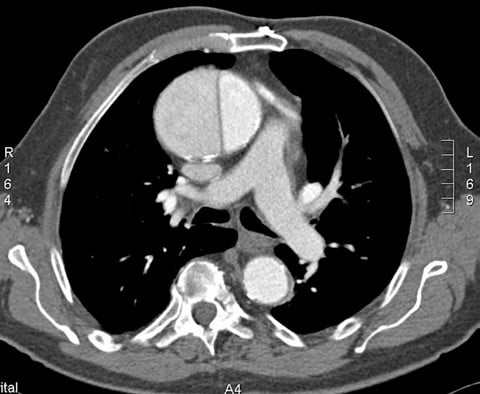

Aortic dissections can be classified using 2 systems: Stanford and DeBakey. The Stanford classification system categorizes dissections according to whether they require surgical repair (type A) or can be managed using medications to control blood pressure (type B).1 Type A dissections affect the ascending aorta, whereas type B dissections do not (see Figures 1 and 2).2 The DeBakey system also categorizes dissections by required medical intervention; however, this classification system details the process, or origination, of the dissection and is divided into types I, II, and III. Type I dissections originate in the ascending aorta, likely continue through the aortic arch, and often involve the descending aorta or even the entire aorta.2 Type II dissections affect only the ascending aorta, while type III dissections solely affect the descending aorta (see Box ).2 The most common aortic dissections occur in the descending aorta.3

Figure 1. Computed Tomography (CT) scan showing an axial view of a Stanford type A aortic dissection. Reprinted with permission from A.Prof Frank Gaillard (Radiopaedia.org, rID: 8886) under the creative commons attribution-noncommercial-share alike 3.0 unported license.